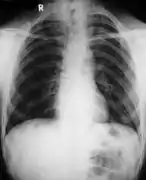

| التشخيص | الأعراض والأشعة السينية التي يتم تأكيدها بالاختبارات الجينية[4] |

هناك سمات مختلفة لخلل التعظم، ويساعد التصوير الإشعاعي على تأكيد التشخيص، ويمكن حساب حجم الترقوة أثناء الحمل باستخدام المخططات البيانية المتاحة، كما يمكن أحيانا ملاحظة العظام الدرزية في الجمجمة.[21]

ويتم التشخيص بوجود العلامات السريرية والإشعاعية النموذجية و/أو عن طريق تحديد متغير الممراض المتباين في الجين RUNX2.[22]